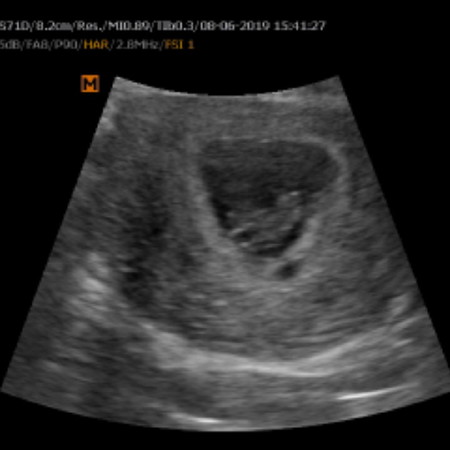

เมื่อคืนมีระดูขาวสีน้ำตาลออกมา กังวลทั้งคืนว่าจะเข้าภาวะเสี่ยงแท้งรึป่าว วันนี้รีบไปหาหมอ สุดท้ายก็เป็นไปตามที่กังวล หมอแจ้งว่าน้องแข็งแรงดี แต่มีถุงเลือดใต้ถุงตั้งครรภ์ แม่จะพยายามอยู่เฉยๆให้ได้มากที่สุดเพื่อที่หนูจะได้อยู่กับแม่...

มีเบบี้แล้ว